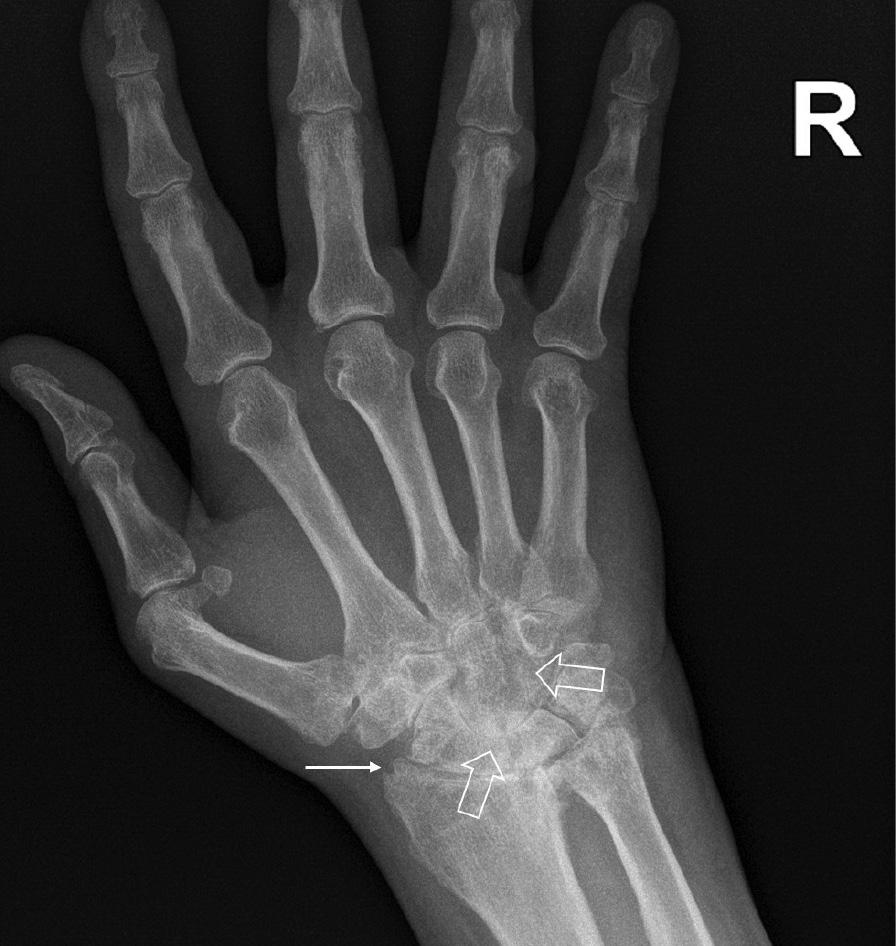

При компьютерной томографии органов грудной клетки данных за «свежие» очаговые и инфильтративные изменения не получено. Увеличения лимфатических узлов подмышечных областей, средостения, корней легких не выявлено. Отмечался усиленный грудной кифоз, обызвествление передней продольной связки, на всем уровне исследования определялись передне-боковые спондилофиты, а также анкилоз большинства реберно-поперечных суставов. По данным рентгенографии кистей (рис. 1, 2) и стоп (рис. 3, 4) диагностированы признаки эрозивного артрита, анкилоз суставов запястья. По данным МРТ крестцово-подвздошных суставов (КПС) определялся неравномерный анкилоз КПС, хрящи по суставным поверхностям неравномерной толщины, примерно на половине протяжении сустава отсутствуют, «суставной промежуток» облитерирован. Неравномерность и нечеткость контура суставных поверхностей за счет множества краевых эрозий справа, единичных – слева, с наличием остеокластоза, в нижнем отделе слева по смежным отделам определяются участки трабекулярного отека, данная находка клинически интерпретирована как двусторонний активный сакроилиит (рис. 5, 6).

Рис. 1. Рентгенограмма левой кисти в прямой проекции. Краевые эрозии суставных поверхностей первого пястно-фалангового сустава (тонкие стрелки), сужение суставных щелей суставов запястья с формированием анкилозов (толстая стрелка)

Рис. 2. Рентгенограмма правой кисти в прямой проекции. Краевая эрозия суставной поверхности лучевой кости (тонкая стрелка), множественные анкилозы суставов запястья (толстые стрелки)